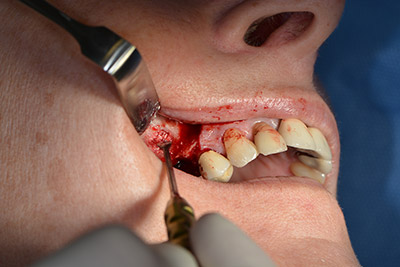

Operatives Vorgehen beim Implantieren

Die klassische Schnittführung (krestal, Entlastung bukkal) und das Präparieren des Mukoperiostlappens erlauben eine gute Übersicht.

In diesem Fall werden Sky Implantate (bredent) verwendet, deren chirurgisches Protokoll die Pilotbohrung mit etwa 1.200/min vorschreibt (Abb. 9).